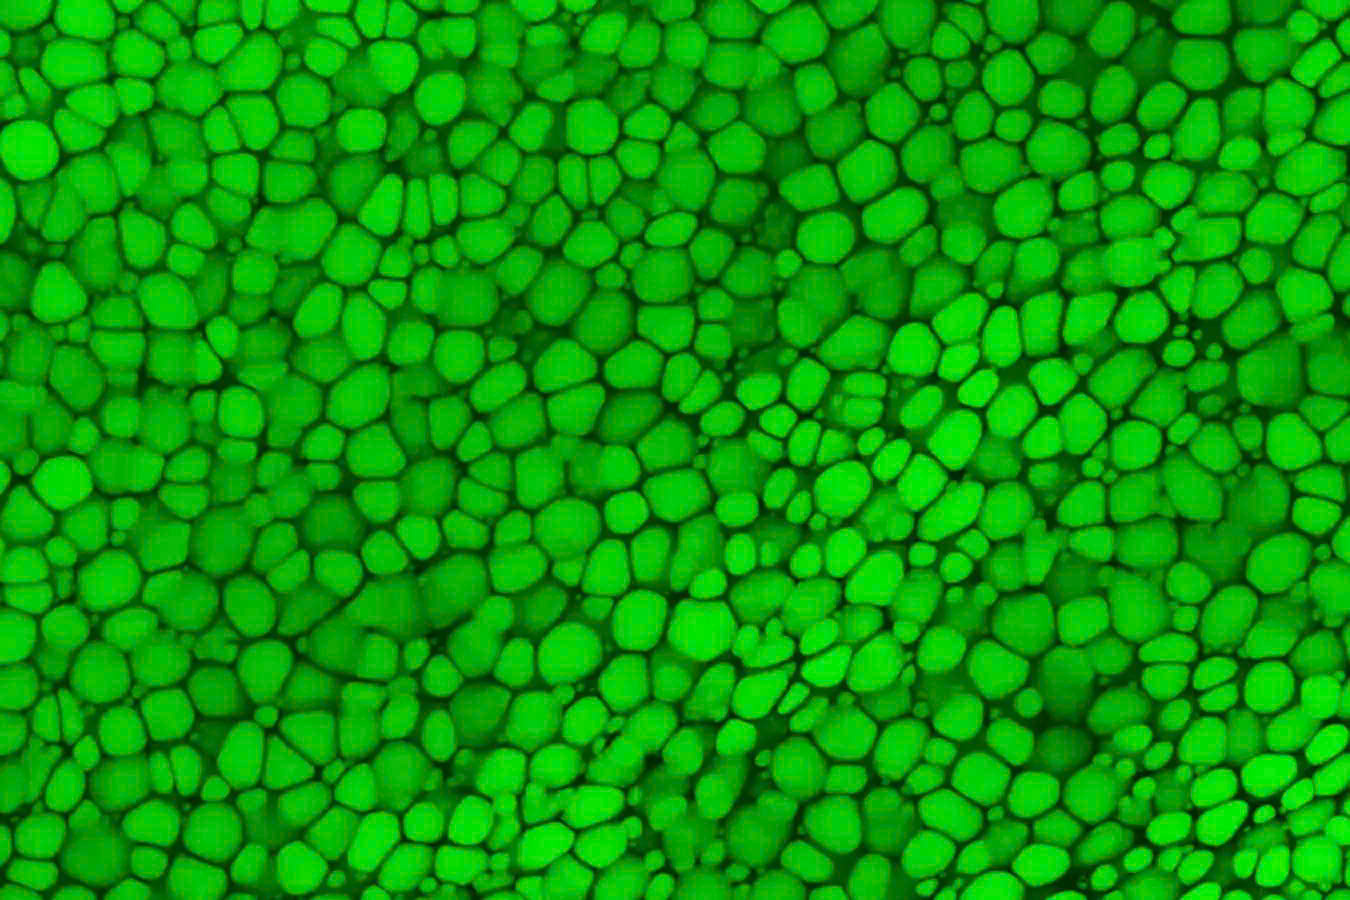

Khác với phần lớn sụn thường dựa vào ma trận ngoại bào (extracellular matrix) để tăng cường độ bền, lipocartilage lại chứa các tế bào giàu chất béo, gọi là “lipochondrocytes”. Những tế bào này tạo ra một cấu trúc hỗ trợ bên trong siêu ổn định, giúp mô duy trì độ mềm mại và đàn hồi, giống như vật liệu đóng gói có các bong bóng khí.

Nghiên cứu mô tả cách các tế bào lipochondrocytes tự tạo và duy trì các kho dự trữ lipid, giữ nguyên kích thước mà không bị ảnh hưởng bởi tình trạng dinh dưỡng. Điều này khác biệt so với các tế bào mỡ thông thường - vốn có thể co lại hoặc phình to theo sự thay đổi của lượng thức ăn.

Các tế bào lipochondrocytes thực ra đã được phát hiện từ năm 1854 bởi TS Franz Leydig - người ghi nhận sự xuất hiện của các giọt mỡ trong sụn tai chuột. Tuy nhiên, phát hiện này hầu như bị lãng quên trong gần 2 thế kỷ. Nhờ vào các công cụ sinh hóa hiện đại và phương pháp hình ảnh tiên tiến, các nhà nghiên cứu tại Đại học California, Irvine đã mô tả chi tiết đặc tính sinh học, vai trò cấu trúc và quá trình trao đổi chất của lipocartilage. Họ phát hiện ra rằng, các lipochondrocytes ngăn chặn hoạt động của các enzym phân hủy chất béo và giảm hấp thụ các phân tử mỡ mới, giữ cho kho dự trữ lipid không bị thay đổi. Nếu mất đi các lipid này, lipocartilage sẽ trở nên cứng và dễ gãy, điều này nhấn mạnh vai trò quan trọng của các tế bào giàu chất béo trong việc duy trì sự bền bỉ và linh hoạt của mô. Ngoài ra, ở một số loài động vật như dơi, các lipochondrocytes được tổ chức thành các hình dạng phức tạp, chẳng hạn như các đường gờ song song trong tai lớn, giúp tăng khả năng nghe bằng cách điều chỉnh sóng âm.